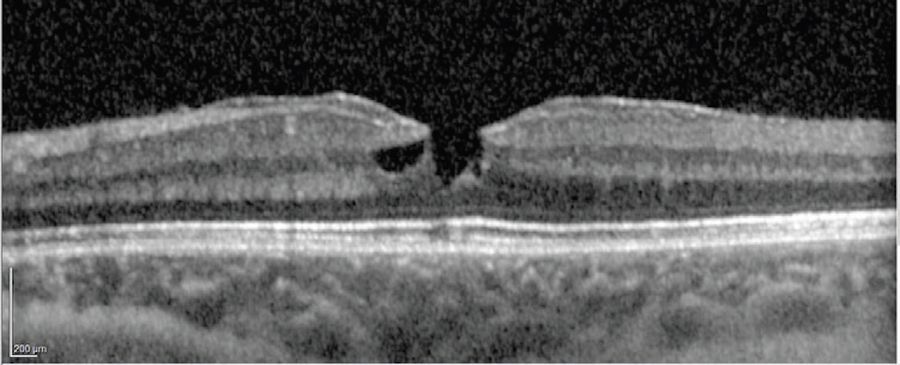

As the membrane was peeled up to the fovea, the intraoperative OCT showed the surgeon when to stop pulling to avoid amputating the epiretinal proliferation. This is critical as the visual cues are not always optimal during this type of maneuver (Figure 4).

The cabbage leaf plume of epiretinal tissue was elevated and then trimmed with the vitreous cutter on shave mode. The surgeon was careful to avoid removing tissue stained yellow by luteal pigments as the goal was to preserve the tissue for reintegration into the fovea. A final scan was performed to confirm traction was removed from the edges of the lamellar hole before the fluid air exchange (Figure 5).

One month post-operatively, the patient had reduced distortion and improved real-world function. He also had improved depth perception and color vision and was able to see the ball better during sports. Further improvement was expected with longer follow-up (Figure 6).